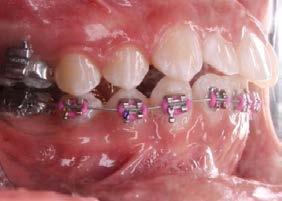

Higiene oral, autopercepción estética y confort en pacientes con ortodoncia

Introducción: Los principales objetivos del tratamiento ortodóncico son corregir las maloclusiones y mejorar la estética dental; sin embargo, el mismo tratamiento puede asociarse a reacciones negativas al requerir aparatología visible que altera aspectos funcionales, estéticos y de higiene oral del paciente. Estos factores podrían influir en la motivación del paciente y determinar una baja adherencia al tratamiento ortodóncico, lo que podría generar retrasos y complicaciones en la estabilización de la oclusión. Objetivo: Evaluar el nivel de satisfacción del paciente con brackets en relación con la higiene oral, el confort y la autopercepción estética. Metodología: Se trata de un estudio transversal con muestreo por conveniencia. Se evaluó el nivel de satisfacción relacionado con la higiene oral, la autopercepción estética y el confort de pacientes tratados en el Instituto mediante un cuestionario validado de autorreporte. Se realizó un análisis descriptivo de la muestra y el cálculo del puntaje del cuestionario; posteriormente, se efectuó un análisis bivariado entre las variables edad, sexo, tratamiento previo y tiempo bajo tratamiento

ortodóncico. Resultados: Participaron 74 pacientes con una edad promedio de 27.1 ± 8.2 años. El 55.4% (n = 41) fueron mujeres. Los hombres presentaron un menor nivel de satisfacción ( = 33.2 ± 6.4) que las mujeres ( = 35.2 ± 8.2). Aquellos pacientes que recibían tratamiento de ortodoncia por primera vez obtuvieron un menor puntaje —y, por tanto, un menor nivel de satisfacción— ( = 33.4 ± 7.6) que quienes ya habían estado sometidos a este tratamiento ( = 35.2 ± 4.6). Los pacientes con hasta 1 año de tratamiento mostraron un menor nivel de satisfacción ( = 33.2 ± 4.6) que aquellos con aparatología por más de 1 año ( = 35.1 ± 3.1). Conclusión: Es importante evaluar, en cada paciente, los factores que puedan influir de forma negativa en su calidad de vida a lo largo del tratamiento, con la finalidad de plantear intervenciones efectivas enfocadas en crear conciencia sobre las expectativas y los posibles inconvenientes derivados del mismo.

Palabras clave: satisfacción, estética, confort, higiene, brackets.

C.D. Octavio Bautista López*, M. en C. José Cuauhtémoc Jiménez Núñez*°, Esp. Gustavo Castillo Salazar* *Instituto de Ortodoncia Bioprogresiva °Facultad de Estudios Superiores Iztacala